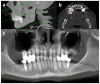

Background: This study aimed to evaluate the diagnostic value of pre-existing computed tomography (CT) examinations for the detection of dental pathologies compared with clinical dental examination in patients with end-stage heart failure. Methods: For this purpose, 59 patients with end-stage heart failure and pre-existing non-dental CT images of the craniofacial region were included. Virtual orthopantomograms (vOPG) were reconstructed. Dental pathologies were analyzed in vOPG and source-CT images. Imaging and clinical findings less than 6 months apart were compared (n = 24). Results: The subjective image quality of vOPG was more often rated as insufficient than CT (66%; 20%; p < 0.01). Depending on examination (CT, vOPG or clinic), between 33% and 92% of the patients could require dental intervention such as treatment of caries and periodontitis or tooth extraction. vOPG led to a higher (80%) prevalence of teeth requiring treatment than CT (39%; p < 0.01). The prevalence of teeth requiring treatment was similar in CT (29%) and clinic (29%; p = 1.00) but higher in vOPG (63%; p < 0.01). CT (stage 3 or 4: 42%) and vOPG (38%) underestimated the stage of periodontitis (clinic: 75%; p < 0.01). Conclusions: In conclusion, available CT images including the craniofacial region from patients with end-stage heart failure may contain valuable information regarding oral health status. The assessability of vOPGs might be insufficient and must be interpreted with caution.